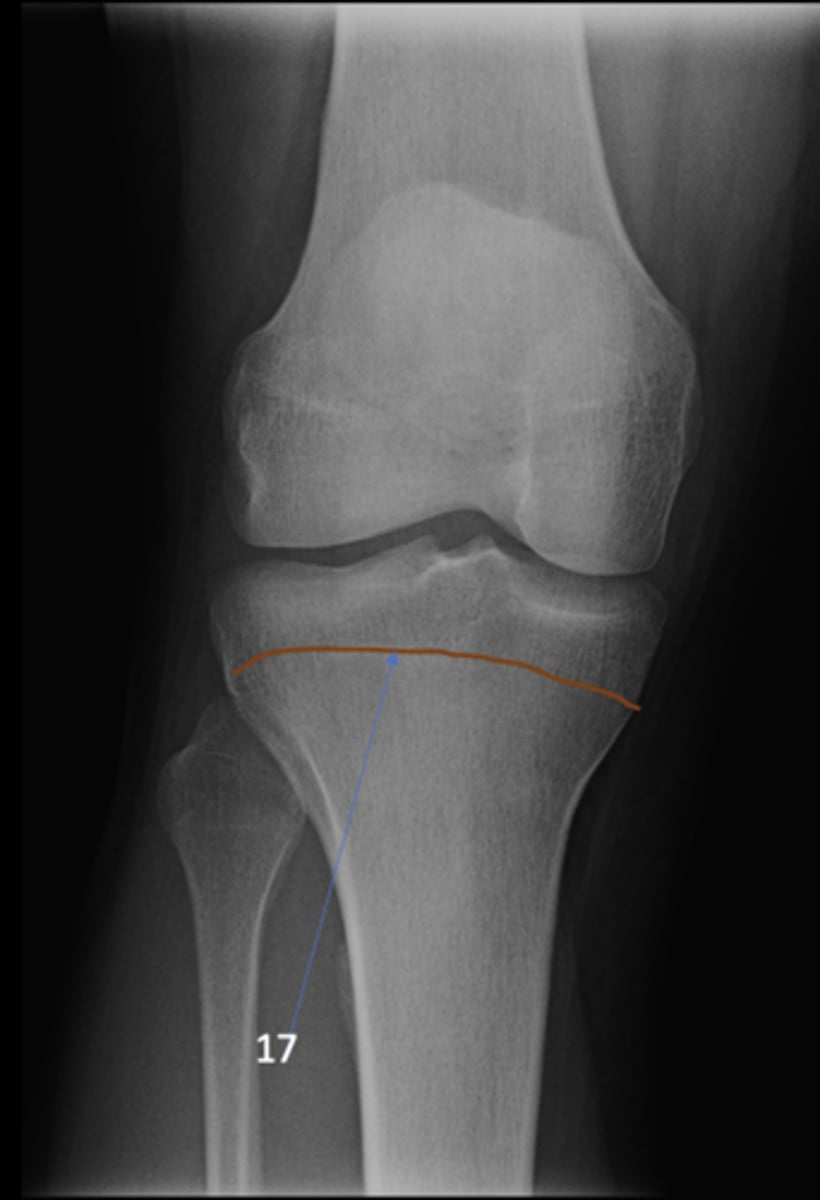

AP knee

View?

49

New cards

Fibular head

ID 1

50

Apex of fibular head

ID 2

51

Fossa for popliteal tendon

ID 3

52

Intercondylar eminence

ID 4

53

Superior aspect of patella

ID 5

54

Lateral femoral condyle

ID 6

55

Medial femoral condyle

ID 7

56

Intercondylar fossa

ID 8

57

Apex of patella

ID 9

58

Lateral femoral epicondyle

ID 10

59

Medial femoral epicondyle

ID 11

60

Tibial tuberosity

ID 12

61

Medial tibial plateau

ID 13

62

Lateral tibial plateau

ID 14

63

Medial tibial condyle

ID 15

64

Lateral tibial condyle

ID 16

65

Physeal scar

ID 17

66

Adductor tubercle

ID 18